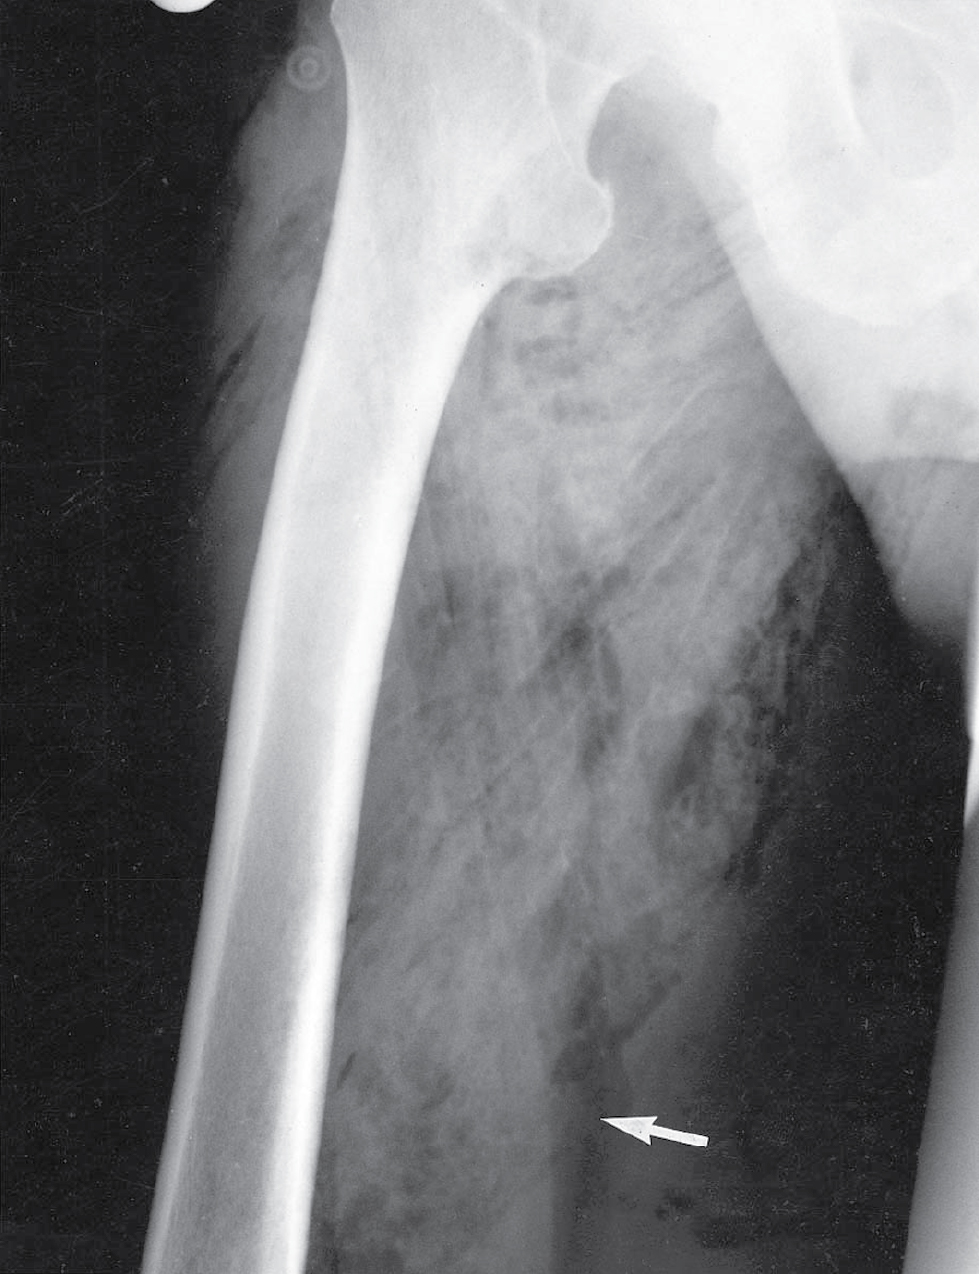

Hoại thư sinh hơi là kết quả khi Clostridium perfringens (trước đây là C. welchii) và các vi khuẩn kỵ khí khác (ví dụ: Bacteroides spp. và streptococci) tăng sinh trong mô hoại tử, tiết ra các độc tố mạnh gây nhiễm độc toàn thân nghiêm trọng. Các độc tố lây lan nhanh chóng tại chỗ và phá hủy các mô lân cận, tạo ra khí gây ra dấu hiệu đặc trưng là tiếng lép bép (crepitus) khi sờ và hình ảnh X-quang điển hình (xem Hình 3.8). Các vết thương chấn thương sâu liên quan đến cơ và các vết thương bị ô nhiễm đất, quần áo hoặc phân là dễ bị tổn thương nhất. Tình trạng này rất phổ biến trong các vết thương chiến tranh—hoại thư sinh hơi chịu trách nhiệm cho số lượng lớn các ca tử vong trong Chiến tranh thế giới thứ nhất.

Bệnh sử

Hình 3.8 Hoại thư sinh hơi. Người đàn ông 46 tuổi này bị các vết rách rộng, bị ô nhiễm ở mặt trong đùi phải (mũi tên) trong một vụ va chạm giao thông đường bộ. Hoại thư sinh hơi đã phát triển, nhanh chóng liên quan đến tất cả các cơ của đùi vì tình trạng này không được nhận ra sớm và mô cơ hoại tử không được cắt bỏ ngay lập tức và hoàn toàn. Lưu ý các vệt bong bóng khí thấu quang (radiolucent) lan rộng dọc theo các mặt phẳng cơ. Bệnh nhân này đã tử vong vì nhiễm độc (toxaemia) mặc dù đã dùng kháng sinh, phẫu thuật và liệu pháp oxy cao áp.